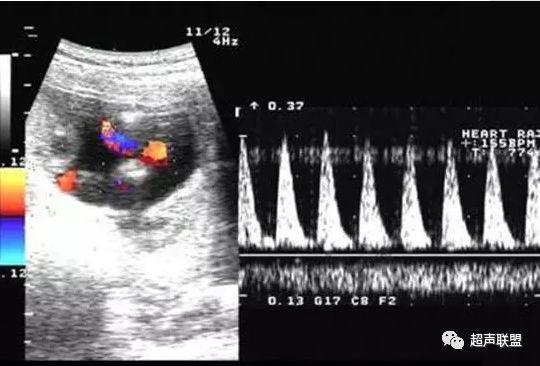

1 胎儿脐动脉测定

缺氧首先出现的变化是舒张末期血流降低,S/D值、RI值和PI值升高。当缺氧进入再分配晚期时,可逐渐出现舒张期血流减少、舒张期血流缺失。失代偿期出现脐动脉血液逆流,舒张期血流倒置。

图1 正常脐动脉血流频谱

图2 脐动脉舒张期血流消失或反向